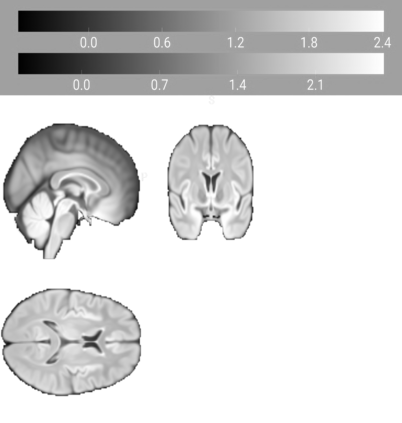

Our knowledge of the organisation of the human brain at the population-level is yet to translate into power to predict functional differences at the individual-level, limiting clinical applications, and casting doubt on the generalisability of inferred mechanisms. It remains unknown whether the difficulty arises from the absence of individuating biological patterns within the brain, or from limited power to access them with the models and compute at our disposal. Here we comprehensively investigate the resolvability of such patterns with data and compute at unprecedented scale. Across 23 810 unique participants from UK Biobank, we systematically evaluate the predictability of 25 individual biological characteristics, from all available combinations of structural and functional neuroimaging data. Over 4526 GPU hours of computation, we train, optimize, and evaluate out-of-sample 700 individual predictive models, including fully-connected feed-forward neural networks of demographic, psychological, serological, chronic disease, and functional connectivity characteristics, and both uni- and multi-modal 3D convolutional neural network models of macro- and micro-structural brain imaging. We find a marked discrepancy between the high predictability of sex (balanced accuracy 99.7%), age (mean absolute error 2.048 years, R2 0.859), and weight (mean absolute error 2.609Kg, R2 0.625), for which we set new state-of-the-art performance, and the surprisingly low predictability of other characteristics. Neither structural nor functional imaging predicted psychology better than the coincidence of chronic disease (p<0.05). Serology predicted chronic disease (p<0.05) and was best predicted by it (p<0.001), followed by structural neuroimaging (p<0.05). Our findings suggest either more informative imaging or more powerful models are needed to decipher individual level characteristics from the human brain.